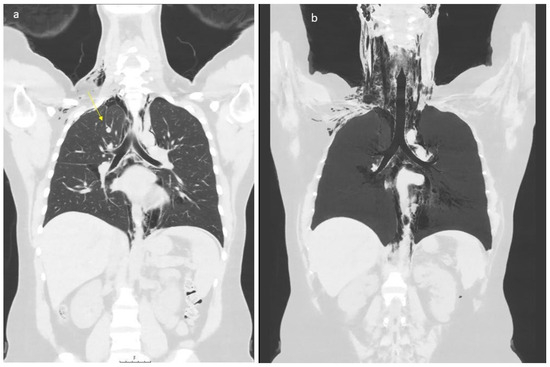

2. Case Presentation